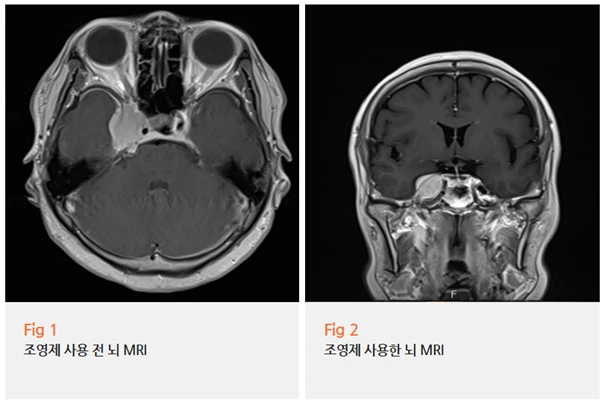

특히 뇌신경을 제대로 보려면 조영제를 사용해서

뇌줄기 부분을 더 꼼꼼히 살펴봐야 한다고 설명드렸어요.

당일 촬영 후 바로 MRI 결과가 나왔어요.

영상을 열어보는 순간...

'역시나'라는 생각과 동시에 '다행이다'라는 생각이 들었어요.

우측 삼차신경을 누르고 있는 뇌수막종이 발견됐거든요.

뇌수막종은 뇌를 둘러싼 막에서 생기는 종양인데요.

위치에 따라 주변 신경을 누르면서 증상을 일으킬 수 있어요.

이 환자분의 경우, 종양이 딱 우측 삼차신경을 압박하고 있었어요.

환자분의 모든 증상과 정확히 일치하는 위치였죠.